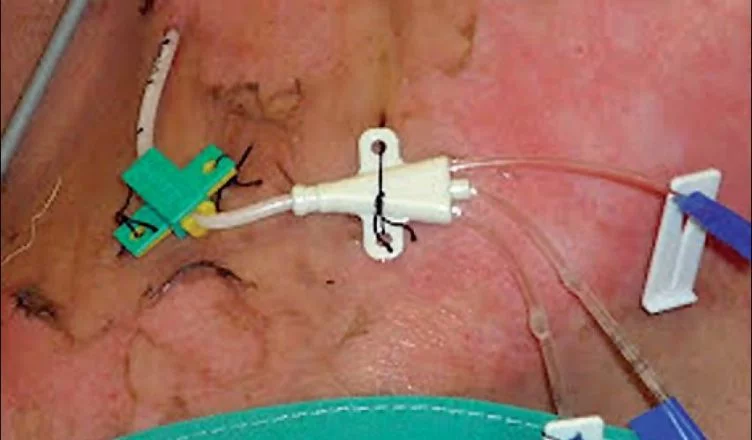

La impregnación de catéteres con antimicrobianos ha demostrado reducir las infecciones relacionadas con el catéter, especialmente cuando la tasa institucional es alta (> 2%). Sin embargo, es importante tener en cuenta que la impregnación de catéteres no reduce la tasa de sepsis (septicemia) ni la mortalidad. Además, se ha observado que los catéteres multilumen tienen un ligero aumento en el riesgo de infección en comparación con los catéteres de un solo lumen. Por lo tanto, se debe insertar el catéter con el menor número de lúmenes necesarios para reducir el riesgo de infección.

En la actualidad, se recomiendan cinco medidas básicas para reducir la incidencia de infecciones relacionadas con el catéter. En primer lugar, se debe realizar un lavado de manos adecuado antes del procedimiento para garantizar una técnica aséptica. En segundo lugar, se debe mantener una técnica aséptica estricta durante la inserción y el manejo del catéter. En tercer lugar, se debe realizar una antisepsia adecuada de la piel con clorhexidina antes de la inserción del catéter. En cuarto lugar, se debe seleccionar el sitio de inserción óptimo, teniendo en cuenta las características del paciente y la experiencia del operador. Por último, el catéter debe retirarse en el momento en que ya no sea necesario para evitar el riesgo de infección. El recambio periódico del catéter por guía no se recomienda, ya que puede aumentar la incidencia de infecciones.